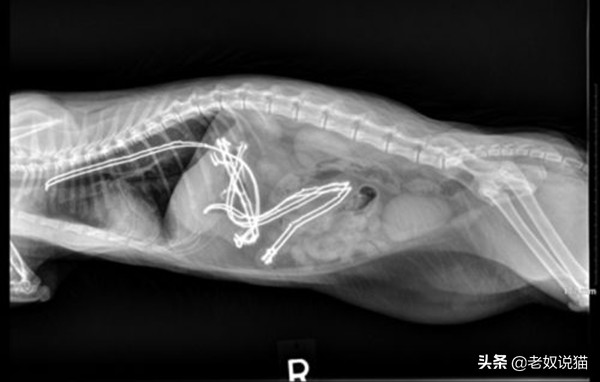

三、误食电线的猫

一只18个月大的小猫肚子中的电线